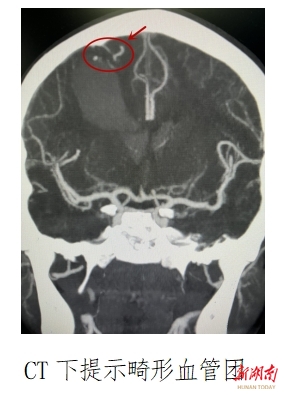

医院接诊后,立即为其完善相关检查,诊断颅内动静脉畸形,左侧肢体肌力3-级,评估患儿病情危重,开通绿色通道转ICU进行进一步监护治疗。在儿童期间出现脑血管畸形出血比较少见,由于患儿年纪小,手术风险极高,但若不及时手术,将危及生命。